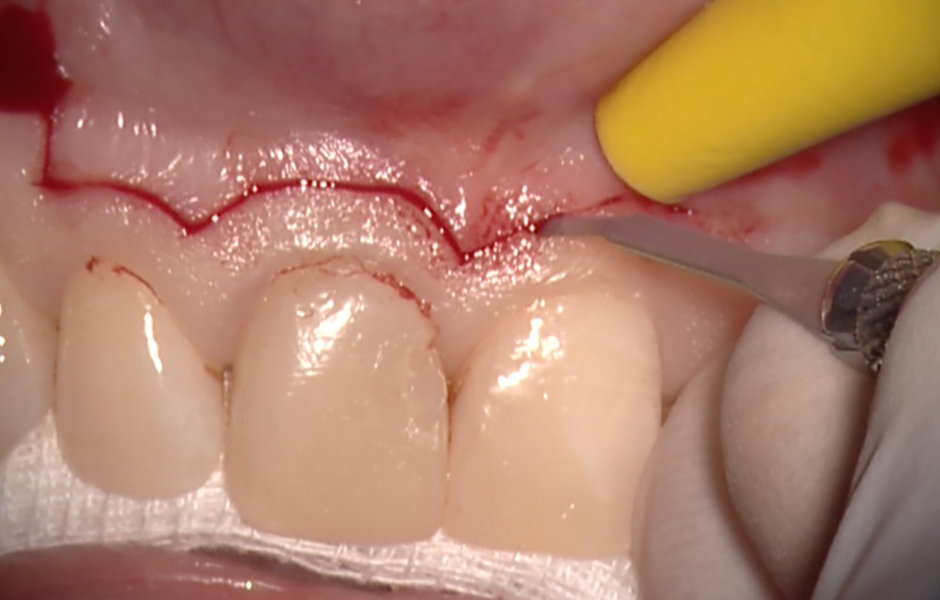

Obr. 1.2: Submarginální incize.

Obr. 4.2: Submarginální lalok.

Pro incizi měkkých tkání používáme mikrochirurgickou čepel a elevace i retrakce laloku musí být maximálně šetrná. Veškerý pooperační diskomfort pacienta je úměrný tomu, jak jemně operatér s chirurgickým lalokem zachází.